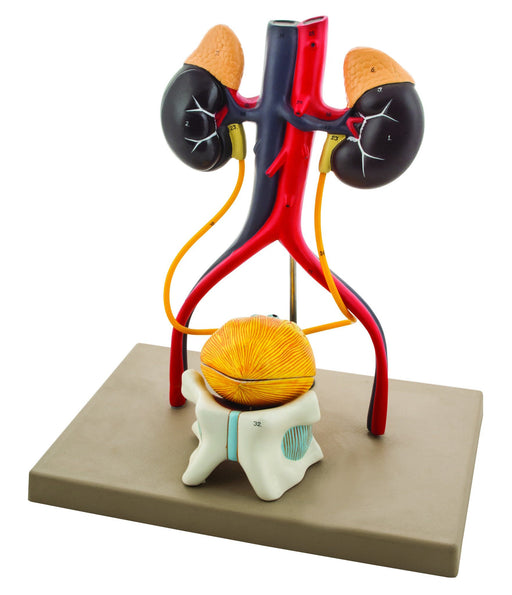

Eisco Life-Size Human Male Urinary System Model, 5 Parts

Approximately life size model includes kidneys with adrenal glands, ureters, urinary bladder, prostate gland, abdominal aorta, inferior vena cava,...

View full detailsAM0356 -